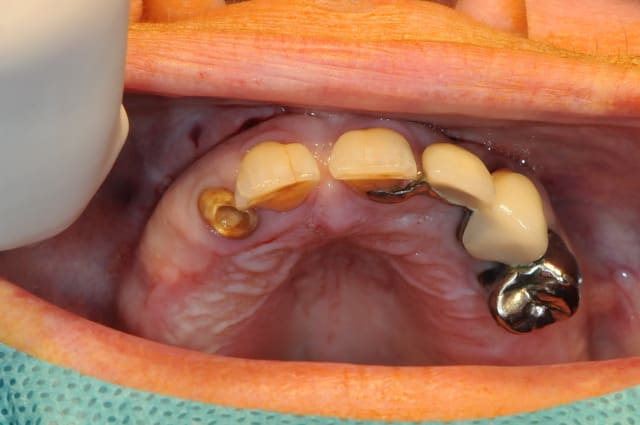

la patiente a été opérée hier et j'ai mis ses prothèses aujourd'hui.

la chirurgie est belle, le cas bien conduit...

pour information, ceux qui ont suivi (oui c'est vrai qu'il fallait s'accrocher...) "le cadeau de Béotien" savent que ce que vous montre D57 n'est pas nouveau...